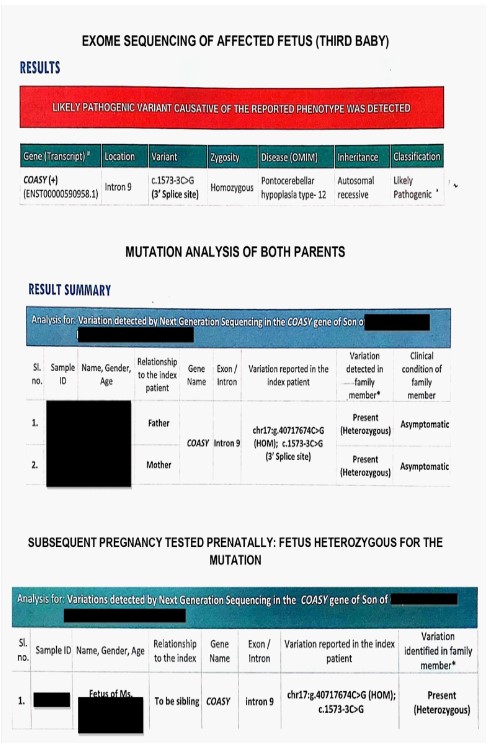

Investigations: Whole exome sequencing in the third baby postnatally identified a homozygous known variant chr17:40717674C>G (GRCh37 or hg19 format) or c.1486-3C>G, depth 207x that affects the position 3 nucleotides upstream of the acceptor splice site of the exon 9 (transcript number NM_025233.7). This variant has been previously reported in patients affected with pontocerebellar hypoplasia type 12, microcephaly and arthrogryposis. This variant has a minor allele frequency of 0.04%, 0.009% and 0.08% in the 1000 genomes, gnom AD and internal databases of Medgenome Labs Pvt Ltd (Bengaluru, India) respectively. The insilico prediction of the variant is damaging by MutationTaster2 software. The reference base is conserved across species. The variant is also reported as likely pathogenic in Clinvar database (https://www. ncbi.nlm.nih.gov/clinvar/variation/599341/). As per American College of Medical Genetics (ACMG) guidelines of classification of variants, the following criteria are met: PM3 criteria for recessive disorders, detected in trans with a pathogenic variant, PM2 criteria absent from controls (or at extremely low frequency if recessive) in Exome Sequencing Project, 1000 Genomes Project, or Exome Aggregation Consortium, PP3 criteria Multiple lines of computational evidence support a deleterious effect on the gene or gene product (conservation, evolutionary, splicing impact, etc.), PP5 criteria reputable source recently reports variant as pathogenic, but the evidence is not available to the laboratory to perform an independent evaluation.

Sanger sequencing of the parents’ blood samples revealed they were heterozygous for the same mutation. The couple was counseled regarding a 25% recurrence risk (autosomal recessive) in all future pregnancies. The options of early invasive testing in each pregnancy or using donor gametes were discussed.

The patient conceived her fourth pregnancy in 2021. The first trimester ultrasound for aneuploidy screening was normal. Chorionic villus sampling was performed at 12 weeks and fetus tested heterozygous for COASY mutation and likely to be unaffected (Figure 6).